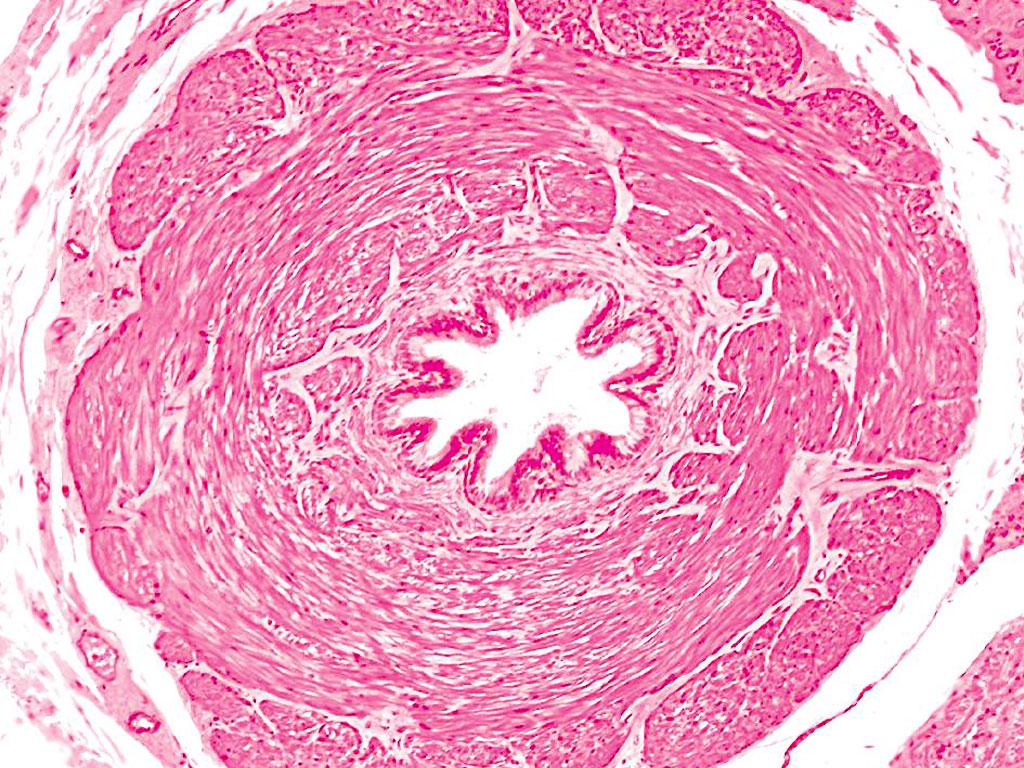

An enlarged prostate can be divided into two types, one is a swollen type and the other one is hyperplasia. In the swollen type of enlarged prostate, prostate cells are enlarged, but the number of cells do not increase. Prostate congestion and swelling causes various kinds of prostate disease from various stimulant factors. This can happen to any man at any age after puberty. The Hyperplasia type of enlarged prostate means prostatic cells are enlarged and the number of cells is increased. Benign prostatic hyperplasia (BPH) occurs because of a sex hormone imbalance, generally in males over 45 years old.

Age-related enlarged prostates mostly result from a declining body function, imbalanced hormone levels from decreased production, decreased testicular and prostate secretion production, atrophying, degenerative changes of the gland and connective tissue hyperplasia in the prostate, all, can enlarge the prostate. An enlarged prostate presses on the urethra and the vas deferens thereby causing urination and ejaculation dysfunction. As the sexual hormones decrease further, functions of other areas of the body also gradually decline